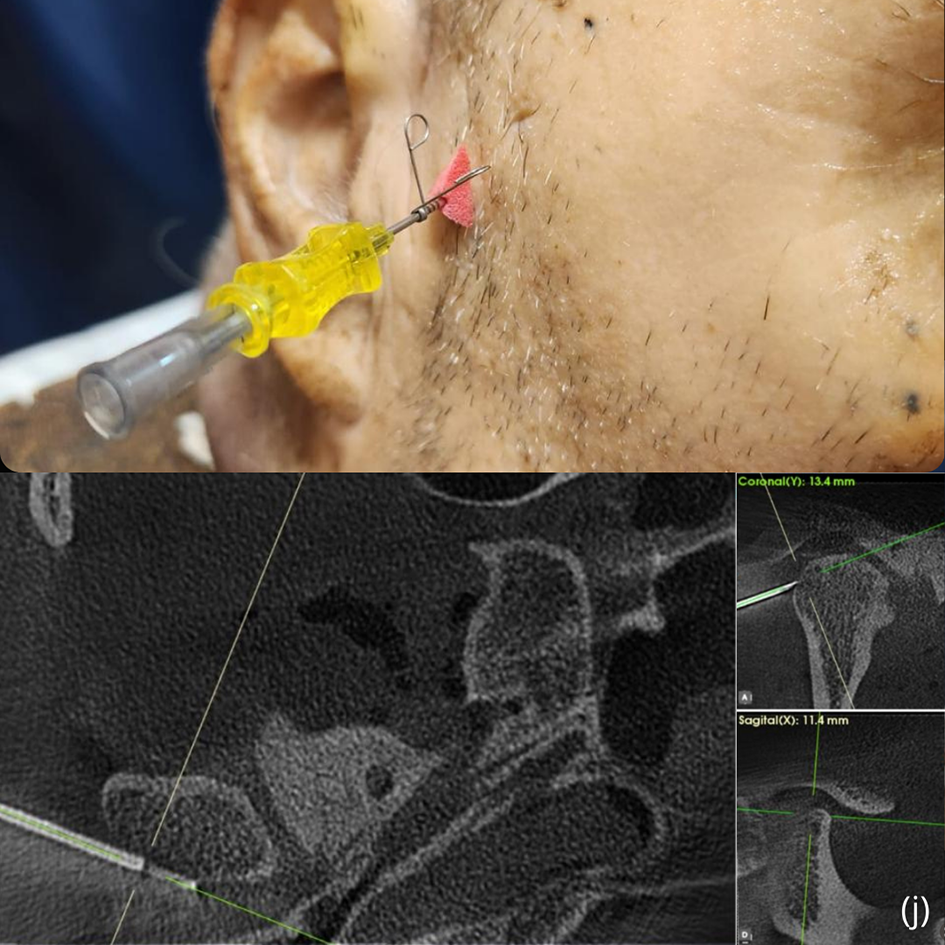

From: Outcomes of modified arthrocentesis using concentric needle and cannula technique with sequential viscosupplementation and orthobiologics in both TMJ compartments

Steps for performing concentric needle and cannula arthrocentesis.